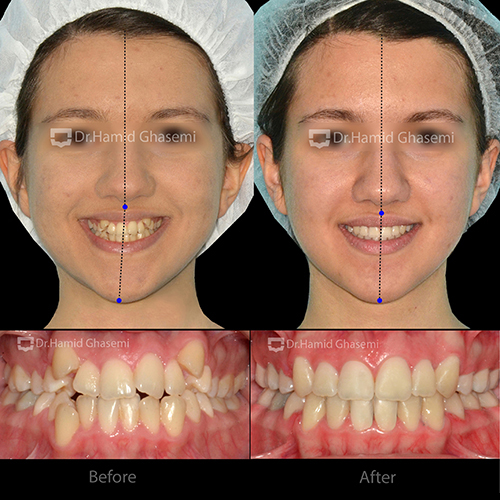

درخواست بیمار:

- دندانهای نیش بیرون زدگی دارد.

- احساس میکنم فک پایین و چانهام کج شده است و مدام در حال بیشتر شدن است.

نوع ناهنجاری:

- رابطه کلاس ۱ اسکلتال و کلاس ۱ دندانی

- تنگی نسبتاً شدید فک بالا

- نیشهای بیرون زده

- انحراف شدید دندانی در فک پایین به میزان ۶ میلی متر به سمت راست

- انحراف چانه به میزان ۴ میلی متر به سمت راست

- انحراف دندانی فک بالا به میزان ۲ میلی متر به سمت چپ

تغییرات (دندانی، اسکلتال و بافت نرم صورت):

- افزایش نمایش و پر شدن لبخند به دلیل افزایش عرضی فک و چیدمان دندانها در قوس فکی عریضتر

- اصلاح انحراف میدلاین دندانی در فک بالا و پایین

- از بین رفتن شیفت فکی به علت ایجاد اکلوژن ایدهآل و دینامیک

- اصلاح موقعیت دندانها و نیز زاویه قدامی جهت کسب زیبایی لبخند و ایجاد طرح لبخند طبیعی با توجه به مشخصات فردی بیمار

- اصلاح موقعیت چانه و رفع انحراف

- اصلاح حالت لبها در موقعیت استراحت و لبخند

- افزایش بیرون زدگی (Vermillion) لبهای بالا ناشی از اصلاح زاویه و موقعیت دندانهای قدامی

- احیای قرینگی بافت نرم صورت به واسطه اصلاح و انحراف میدلاین دندانی و موقعیت چانه